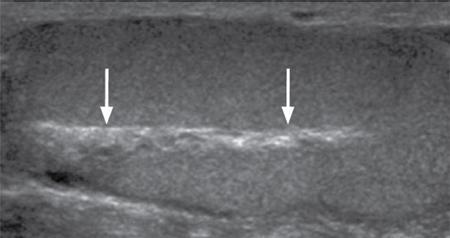

ULTRASOUND MALE PELVIS Vivek Kashyap Pelvic ultrasound is a noninvasive technique for imaging major organs in the pelvis including the bladder, prostate gland, blood vessels and bowel. It is usually the first line of investigation to evaluate the prostate and seminal vesicles. Ultrasound is a safe and reliable imaging resource to assess the pathology and guide towards appropriate treatment plan. To start pelvic ultrasound with evaluation of the shape and size of the bladder. The bladder is in the pelvis, posterior to the pubic bones. The peritoneum is seen superior to the urinary bladder and reflecting over the anterior surface. The trigone is a triangular area bounded by the two ureteric and urethral orifices. The urinary bladder has an outer loose connective tissue layer, known as subserosa which bounds the three muscular layers. The innermost is the mucosal layer. These layers should be smooth and uniform and the thickness will depend on the bladder distension. Prostate can be seen posterior to the urinary bladder when examined in transverse views. Prostate is seen at the inferior part of the urinary bladder in sagittal view (Fig. 11.1.1.1A). It should be examined in both the views. Urinary bladder neoplasms are usually seen arising from the walls of the urinary bladder, though these can be of varying shapes, usually are polypoidal and can present as solitary or multiple lesions, often seen on opposing walls of the urinary bladder, also known as ‘kissing lesions’ (Fig. 11.1.1.1B). For evaluating the bladder, it should be moderately filled. An overfilled bladder will cause patient discomfort and can compress structures posterior to it. The bladder should be scanned in the transverse and sagittal planes and prevoid volume is calculated. After micturition, the length, width and height (cm) of the bladder are recorded in sagittal and horizontal planes. The postvoid residual volume is calculated using the formula: Postvoid residual volume (PVR) = Length × Width × Height × 0.5 Normally there is no residual urine. PVR less than 50 is usually considered as insignificant. PVR volume more than 100 mL is considered significant in adults. Ureteric jets are the normal visualization of the physiological periodic efflux of urine from the distal ureter into the bladder. Ureteric jet can be appreciated by colour Doppler examination as a sudden burst of colour in the bladder that lasts for a few seconds. Bladder wall thickening is considered significant if >3 mm in a distended bladder and >5 mm in a collapsed bladder; however, it’s a good practice to fill the bladder completely before doing the investigation (Fig. 11.1.1.2). The common causes of bladder wall thickening include: Urinary bladder diverticula are examined very well on ultrasound (Fig. 11.1.1.2). Congenital diverticula, also known as Hutch diverticula are generally seen near the ureteral orifices. Acquired diverticula are generally due to bladder outlet obstruction. Bladder mucosa herniates through weak portions of the bladder walls, this may create diverticula with a narrow neck leading to urinary stasis, which may in turn cause stones, infection tumours or ureteric obstruction. These diverticula appear as an outpouching sac from the bladder and urine may be seen flowing into or out of the diverticulum. Intraluminal pathologies such as vesicle calculus are seen within the bladder, calcifications are seen in the bladder wall or in the mass lesions. Faeces, inflammatory or neoplastic bowel lesions, enlarged lymph node, masses from nerves, vessels and bones, ectopic or transplant kidney, accessory spleen can also be diagnosed from pelvic ultrasound. Ultrasound use for the male pelvis even though limited, has great importance to detect free abdominal fluid, undescended testes in the groin and hernias. Dilated urethra in posterior urethral valves, and occasionally a valve itself can be seen in real-time sonography, aided by transperineal scanning. Prevoid and postvoid volume Wall thickness Ureteric jets Size and volume Morphology of central and peripheral zone Morphology of seminal vesicles ULTRASONOGRAPHY INGUINOSCROTAL REGION V. Sivakumar Ultrasonography is the ideal noninvasive imaging modality for evaluation of scrotal abnormalities. It is capable of differentiating the most important aetiologies of acute scrotal pain and swelling, including epididymitis and testicular torsion, and is the imaging modality of choice in acute scrotal trauma. In patients presenting with palpable abnormality or scrotal swelling, ultrasonography can detect, locate and characterize both intratesticular and extratesticular masses and other abnormalities. A 12–17 MHz high-frequency linear array transducer provides excellent anatomic detail of the testicles and surrounding structures. In addition, vascular perfusion can be easily assessed using colour and spectral Doppler analysis. In most cases of scrotal disease, the combination of clinical history, physical examination and information obtained with ultrasonography is sufficient for diagnostic decision making. This review covers the normal scrotal anatomy as well as various testicular and scrotal lesions. Ultrasound is the widely used modality of choice for evaluation of scrotal abnormalities. Scrotal ultrasound is very helpful differentiating the most common causes of acute scrotal pain and swelling, including epididymoorchitis and torsion testis, and is the choice of investigation for acute scrotal trauma. Detection, localization and characterization of intratesticular and extratesticular pathologies are made easy using scrotal ultrasound. A 12–17 MHz high-frequency linear probe or transducer provides valuable anatomical information of testes and adjacent structures. Colour and spectral Doppler analysis can be used in assessing the vascular perfusion status of scrotal structures in real time. In most cases of scrotal disease, the combination of course, clinical history, clinical examination and imaging finding on ultrasound and Doppler is very essential in the diagnosis of scrotal diseases. Clinical examination sometimes leads to nonspecific signs and symptoms such as vague scrotal pain, suspicious scrotal mass or swelling. In such situations, ultrasound is useful in diagnosing and characterizing intratesticular and extratesticular pathologies as well as distinguishing benign or malignant lesions as well as identifying conditions requiring emergency surgical attention. Scrotum is a fibromuscular sac like structure divided into two hemiscrotum, right and left by a midline septum or raphe. Both the testes are located within the scrotum. The normal testicle appears like a ovoid structure with a homogeneous intermediate echogenicity and measuring approximately ~ 5 × 3 × 2 cm (craniocaudal, anteroposterior, width) (Fig. 11.1.2.1) Epididymis is elongated comma-shaped structure abutting posterior margin of testes and divided into three parts, head, body and tail. Epididymal head is seen in close relation to superior pole of testis and appears iso- to hyperechoic to the adjacent testicular parenchyma (Fig. 11.1.2.2). Epididymal body and tail can be visualized posterior to and along inferior pole of the testes and appears isoechoic to testicular parenchyma. A separate fibrous capsule called the tunica albuginea in each of the hemiscrotum encloses the testes and epididymis. This fibrous capsule can be noticed as a thin echogenic band like structure surrounding the testis on ultrasound. Tunica albuginea is covered by the tunica vaginalis, which is a remnant of processus vaginalis. It represents a closed sac of peritoneum and has two layers. The visceral layer of tunica vaginalis is seen lining the tunica albuginea of testis and is separated from the parietal layer that lines the inner aspect of the scrotal wall by minimal fluid-containing interspace. The tunica albuginea extends into the posteromedial aspect of testis to form the mediastinum testis (Fig. 11.1.2.3). It contains ducts, nerves and blood vessels. On ultrasound mediastinum is noticed as a thin echogenic band like structure. There are numerous fibrous septa extending from mediastinum testis dividing the testicle into multiple small lobules. The lobules are made of seminiferous tubules, they converge to form the tubuli recti, which are the testicular ducts that open into the rete testis. In around 20% of population, the rete testis can be visualized as a hypoechoic area adjoining the mediastinum testis. Efferent ductules coming out of rete testis can be seen draining into the epididymal head. From epididymal head, the ducts converge into a single duct in the epididymal body and exit the epididymal tail as the vas deferens. The vas deferens runs along the contents of spermatic cord and courses superiorly within the inguinal canal. The spermatic cord contains nerves, testicular artery, deferential artery, cremasteric artery, lymphatic ducts and the pampiniform venous plexus. On ultrasound the spermatic cord appears as an echogenic band like structure within the inguinal canal. The major vascular supply to the testes is by the paired testicular arteries which arise from the abdominal aorta. The testicular artery after entering into the tunica albuginea branches into capsular arteries and recurrent rami branches which then courses centrifugally into the mediastinum. A collateral circulation comprising of deferential artery and the cremasteric artery is also seen. Arterial supply to the remaining parts of the scrotum is from the pudendal arteries, which arise from the internal iliac artery. Anatomic relationships of the vascular structures within the spermatic cord are important and alteration in this normal relationship is associated with few pathologies. High insertion of tunica vaginalis to the spermatic cord, the bell-and-clapper deformity leaves the testes to rotate freely within the tunica and can lead to intravaginal testicular torsion. The pampiniform venous plexus continues as the testicular vein in the deep inguinal canal. The right testicular vein drains directly into the inferior vena cava (IVC) whereas the left testicular vein drains into the IVC via the left renal vein. Epididymal and testicular appendages usually represent embryologic remnants. They are better visualized in ultrasound in the presence of a hydrocele. The appendix of testis (hydatid of Morgagni) can be visualized as an isoechoic, oval structure between the epididymis and testis (Fig. 11.1.2.4). An appendix of epididymis is a pedunculated structure arising from the epididymal head, which is also isoechoic to testicular tissue. Ultrasound of the scrotum includes both greyscale and colour Doppler evaluation of testicles, epididymis on both sides and the scrotum. Spectral Doppler evaluation can be used to demonstrate normal waveforms in the testicular artery and vein. For scanning a high frequency, broad bandwidth 17–5 MHz or 12–5 MHz linear array transducer is used. With the help of a towel placed under the scrotum the testicles and scrotum are elevated. With another towel the patient retracts and covers his penis. Initially with a side-to-side large-field imaging both testes are demonstrated using both greyscale and Doppler techniques. Echogenicity and perfusion of each testis is examined. Each testis is imaged longitudinally in medial, mid, lateral portions and transversely in upper, mid and lower pole regions. Three-dimensional (3D) measurement of each testicle is taken (length, width and height). Epididymis evaluation includes longitudinal and transverse imaging including head, body and tail. Colour Doppler study of testes and epididymis is done on both sides and status of capsular and centripetal arteries assessed and documented. Spectral waveform of both arterial and venous flow is documented on each side. Optimization of colour and spectral Doppler analysis is done to clearly depict low velocity venous flow. Colour Doppler imaging in various planes and comparison with contralateral asymptomatic testis is done in specific evaluation for testicular torsion. Scrotal survey should be done for extratesticular findings such as hydrocele, varicocele or calcification/scrotolith. The pampiniform plexus of veins should be evaluated for the diameter and its augmentation on standing position or Valsalva manoeuvre. Scrotal wall should be assessed for thickening and oedema. Extratesticular and intratesticular pathologies, either focal or diffuse should be identified and characterized using grey scale and Doppler imaging techniques appropriately. Focal lesions should also be measured three dimensionally. Presence of solid, cystic, calcific, complex cystic areas in the lesion should be characterized. Labelling of the lesion/images in respect to location (upper, middle or lower), orientation (longitudinal and transverse) and position of the patient (supine, decubitus and standing) is done. Labelling of the lesion/images during specific manoeuvres such as Valsalva should also be done. For scanning a high frequency, broad bandwidth 17–5 MHz or 12–5 MHz linear array transducer is used. Initially with a side-to-side large-field imaging both testes are demonstrated using both greyscale and Doppler techniques. Echogenicity and perfusion of each testis and epididymis should be examined. Each testis is imaged longitudinally in medial, mid, lateral portions and transversely in upper, mid and lower pole regions. Epididymis evaluation includes longitudinal and transverse imaging including head, body and tail. Spectral waveform of both arterial and venous flow is documented on each side. Ultrasound and colour Doppler are the first-line imaging modality for acute or chronic scrotal pathologies. Ultrasound is a safe and reliable imaging modality for demonstration of scrotal anatomy, localization of testicular pathologies and for assessing the vascularity. Since most of the testicular pathologies have characteristic ultrasound appearance, ultrasonography is able to clearly guide patient management and prevent unnecessary surgery. TRANSRECTAL ULTRASOUND OF PROSTATE Vivek Kashyap Carcinoma prostate is the second most common cancer in the world and the sixth leading cause of cancer death in men. The worldwide burden of prostatic cancer is estimated to touch 1.7 million new cases and 499,000 deaths by 2030. The prostate is an unpaired glandular organ. The average dimensions in a healthy young adult is 3.75–4.00 × 2.5–3.00 × 3.1–3.8 cm (w × h × l) and the volume ranges from 20–25 cm3. It produces the prostate-specific antigen (PSA) a glycoprotein which is an ingredient of the semen and is responsible for liquefying semen. The prostate has endocrine properties as it produces prostaglandins E, F and A, spermidine and spermine. It is also the place of the conversion of testosterone into dihydrotestosterone under the influence of the 5-α-reductase enzyme. COMMON INDICATIONS FOR A TRANSRECTAL ULTRASOUND (TRUS) OF PROSTATE Assessment of prostate size Abnormal growth within the prostate Male infertility Elevated PSA levels Detecting disorders within the prostate Micturating difficulties Because ultrasound provides real-time images, it can be used to guide biopsies which may be necessary, FNAC or tissue biopsy as well as brachytherapy seed placements. Transrectal US is a widely used clinical imaging method. For confirming the diagnosis of prostatic cancer, a systematic needle biopsy with US guidance is the diagnostic test of choice (Fig. 11.1.3.1). To understand the images produced by transrectal US, it is important to understand the zonal anatomy of the prostate gland. The outer zone is the peripheral zone, inner to it the transitional zone, then central zone and periurethral zone. The peripheral zone is the largest, containing almost 70% of the prostatic tissue and is the site of most prostatic cancers. It is separated from inner zones by a surgical capsule which may be seen as hyperechogenic line The transitional zone is much smaller (about 5%) and is seen as two small glandular areas such as saddle bags adjacent to proximal urethral segment. The central zone constitutes almost 25%–30% of the total gland size. The ducts of vas deferens and seminal vesicles pass through this zone. This zone shows only about 5% incidence of cancers and appears relatively resistant to diseases. The periurethral zone is only about 1% and encircles the urethra. The commonest features of benign prostatic hyperplasia are hypoechoic enlargement of inner zone. Other features could be calcifications along with diffuse or well-circumscribed rounded hypoechoic or hyperechoic nodules along with degenerative or retention cysts (Fig. 11.1.3.2A,B). Well-circumscribed hypoechoic nodules arising in the transitional zone may become so large that they distort the gland and appear to be in the peripheral zone and these are invariably benign. In cases of hyperplastic nodules occurring in the peripheral zone, they will appear as firm to hard nodules and should undergo a biopsy. We must remember that prostatic enlargement may not correlate with urinary symptoms in all cases, therefore any urinary dysfunction calls for evaluation of the prostate, bladder, urethra, spine and CNS. Transvesicle ultrasound is done to evaluate prostate size, median lobe, bladder trabeculations, diverticula, tumours or calculi. Patients who have had TURP done before will invariably show a defect in the gland. However, the size of the defect will not always correlate with the amount of tissue removed during the procedure, nor does it correlate well with the success of the procedure. This is a condition of inflammation of the prostate and seminal vesicles. The prostate may appear normal in prostatitis or there may be a focal mass, ejaculatory duct calcification, irregularity or thickening of the capsule, periurethral glandular irregularity, dilated periprostatic veins and distended seminal vesicles. Chronic granulomatous prostatitis can present as diffuse large or small hypoechoic zones or a solitary hypoechoic lesion. The examination is generally painful and colour Doppler may show a very vascular focus (Fig. 11.1.3.3A). If we see a hypoechoic mass within the prostate with or without internal echoes may be an abscess. Common ones are degenerative or retention cysts in hyperplastic nodules. These are generally symptomless, unless they become large (Fig. 11.1.3.3B). Prostatic utricle cysts are in the midline and are caused by dilatation of prostatic utricle. These can be associated with unilateral renal agenesis and rarely contain spermatozoa. Other type of cysts seen are Mullerian duct cyst which are a little lateral and are also tear drop and do not contain spermatozoa. Ejaculatory duct cysts are small and could be a small diverticulum of the ejaculatory duct or an obstruction. These can be fusiform in shape with pointed ends and contain spermatozoa. These are associated with infertility. Seminal vesicle cysts are another type, which could be large and solitary, associated with ipsilateral renal agenesis sometimes. In cases of male infertility, transrectal sonography has an important role in assessment of causes of azoospermia for ejaculatory duct obstruction or anomalies (about 1%–2%) Seminal vesicles, dilated ejaculatory ducts and midline cysts can suggest obstruction. There is a strong association of absence of vas with cystic fibrosis. The results of transrectal scanning in infertile men with azoospermia can be normal appearance (25%), bilateral absence of vas deferens (34%), bilateral occlusion of the vas, seminal vesicles or ejaculatory ducts by calcification or fibrosis (16%), unilateral absence of vas (11%), obstructing cysts (9%), ductal obstruction due to calculi (4%). Some of these causes, more so in distal two-thirds could be surgically correctable and therefore it is essential that careful evaluation is done. Haematospermia is blood in the semen. This could be acute (red in colour) or dark brown (old blood). Nonspecific inflammation of the prostate or seminal structures is the most common cause, resolving on its own after some time. We should exclude tumours or infection of prostate or bladder. Transrectal scanning can detect calculi or cysts in the seminal vesicles or ejaculatory ducts (Fig. 11.1.3.4). Other causes includes vascular malformation or sometimes following a prostatic biopsy. Ultrasound elastography is an imaging technique for mapping tissue stiffness of the prostate gland. Two elastography techniques that have developed are strain technique, and second, shear wave technique. The tissue stiffness information provided by US elastography can improve the detection rate of prostate malignancy and provide guidance for biopsy. Prostate elastography has high sensitivity for detecting prostate malignancy and shows high negative predictive values, ensuring that few malignant lesions will be missed. Transrectal US has been used for local staging of prostate cancer in some studies but is generally considered insufficient. Extracapsular extension (ECE) can be demonstrated by the bulging or irregularity of the capsule adjacent to a hypoechoic lesion. Seminal vesicle invasion (SVI) is diagnosed by demonstrating the extension of a lesion at the base of the prostate into a seminal vesicle. Solid hypoechoic lesions within the seminal vesicles or asymmetry of the seminal vesicles are indirect indicators of disease extension. Additional transrectal US-guided biopsies of the seminal vesicles can be performed when extra prostatic extension into the seminal vesicles is suspected. Studies performed in the 1980s showed when cancers are larger (stage T3) and more readily palpated, sensitivity for detecting ECE and SVI by transrectal US was more than 80%. With advent of colour duplex and power Doppler US, there has been renewed interest in the use of transrectal US to identify cancer in hyper vascular areas, with only modest improvements in sensitivity and specificity. Transrectal US continues to play an important role in therapy for directing brachytherapy seeds into the accurate location within the prostate. Cryotherapy and focal ablation of the prostate cancer also requires transrectal US guidance. Future developments in transrectal US may include the utilization of microbubble contrast agents and targeted imaging. Microbubbles coated with surface ligands that preferentially target tumour neovascularity can be used. Because of the large size of these bubbles (1 m), these agents can provide information about large-vessel microvascularity which can be useful in detecting cancer; however, if in future smaller-size microbubbles are available, they can further improve detection. Seminal vesicles have symmetric appearance and lie cephalic to the prostate and posterior to the bladder. They have a typical ‘bow-tie’ appearance in transverse scans, and a club or tennis-racket shape in longitudinal scan. They show homogenously fine echoes but less echogenic than prostate. Volume of seminal vesicles tends to shrink after the fifth decade. TRUS provides excellent anatomical details of seminal vesical and ejaculatory ducts. TRUS helps to diagnose calculi in seminal vesicle or ejaculatory duct. Also TRUS provides high-resolution imaging of the prostate, seminal vesicles and vas deferens and is the investigation modality of choice in diagnosing congenital and acquired abnormalities implicated in the cause of obstructive azoospermia. USG FEMALE PELVIS M. Alamelu Ultrasound is a noninvasive, easily available and informative investigation. A skilfully done and well-interpreted ultrasonogram image usually obviates the need to proceed to additional expensive and composite cross-sectional imaging tests. Ultrasound is high-frequency sound waves (20 kHz), inaudible to human that can be safely transmitted into human body to scan the tissues. Images produced in ultrasound depend on the mechanical properties of tissues and their distance from the source of the sound as it will differentially affect the energy of the sound waves (Table 11.1.4.1). As the frequency of the transducer scan-head increases, the resolution increases and penetration into the body tissue decreases. The piezoelectric crystals convert electric energy into mechanical energy and sound waves are produced. Pelvic pain Pelvic masses Dysmenorrhea (painful menses) Amenorrhea Abnormal uterine bleeding Follow-up of previously detected abnormality Infertility Pelvic infection Evaluation after pelvic surgery, delivery or abortion To localize intrauterine device (IUD) Screening for genital tract malignancy in high-risk patients Pelvic organ prolapse The transducer is placed longitudinally over the adequately distended bladder, the gain settings to be adjusted for optimal visualization (Fig. 11.1.4.1). Scanning is to begin longitudinally from midline between umbilicus and pubic symphysis, angulated to the sides, moved laterally to both right and left side (Fig. 11.1.4.2). Next, scan transversely beginning from pubic symphysis down to umbilicus upwards (Fig. 11.1.4.3). If needed, patient can be asked to turn obliquely (30–40 degrees) for evaluation of ovaries and adnexa (Fig. 11.1.4.4). The following should be assessed: The overall length of uterus is evaluated in the sagittal view from fundus to cervix (to the external os, if seen). The length can either be measured as a straight line from fundus to cervix by using the outer-to-outer technique or can be measured from fundus of uterus along the endometrial lining and endocervical canal using the outer-to-outer technique (Fig. 11.1.4.5). The anteroposterior measurement of the uterus is made in the sagittal view from its anterior to posterior uterine walls. The maximum width can be measured in the transverse or coronal plain. The cervical component should be excluded from uterine length measurement for volumetric assessment of uterine corpus. The neonatal uterus, with exposure of maternal hormones is well depicted with US. The uterus is more narrower and shorter, with a mean length of 3 cm in infants of 4–12 months. Cervix attains a tubular shape and is proportionate to the uterine body. After 1 year of age, uterine length gradually increases and rapid growth occurs as the girls approach puberty. The mean uterine length 3 cm or less for young girls, 3–4.5 cm for prepubertal girls and 5–8 cm for pubertal girls. During puberty, the uterine body becomes more thicker and rounded, pear shaped, with a ratio of uterine body-to-cervix – 1.5:1, an appearance similar to that in women of reproductive age (Table 11.1.4.2). Source: J.E. Langer, E.R. Oliver, A.S. Lev-Toaff, B.G. Coleman, Imaging of the Female Pelvis through the life cycle, Radiographics 32 (2012) 1575–1597. H.J. Paltiel, A. Phelps, US of the pediatric female pelvis, Radiology 270 (2014) 644–657. Depending on the extent of the urinary bladder distension the normal uterus assumes a number of positions. Depending on the relationship of the angle of the long axis of the uterine body to the long axis of the cervix (flexion) and the long axis of the uterus to the long axis of the vagina (version) various positions are described. The most common position for uterus is in anteversion and anteflexion (Fig. 11.1.4.6). When the uterus is positioned in retroversion or retroflexion, it will be difficult to image transabdominally in most cases and is imaged well with an endovaginal transducer. Following every delivery, the uterus of parous women becomes more thick and round. After caesarean delivery, the uterus typically appears more elongated with variable deformity or thinning at the site of the lower uterine incision. The postmenopausal uterus is atrophied and small. The reduction in uterine size is most rapid during the first decade after menopause. The range can vary between 3.5 and 6.5 cm in length and 1.2 and 1.8 cm in anteroposterior dimensions. The endometrium should be assessed for the thickness, presence of focal abnormalities, its echogenicity, and the characteristics of fluid or masses in the cavity. The endometrium has a variable echogenicity, depending on its water content and the cellular density, that varies with the hormonal status of the patient. Neonatal uterus – The endometrium appears as echogenic line and endometrial fluid is often seen, due to residual effect of maternal hormones. The endometrium becomes less obvious, a thin echogenic line seen centrally in only 50% of girls of prepubertal age. The postpubertal endometrium is easily visible with transabdominal US and varies in thickness with the phases of the menstrual cycle. The thickness of endometrium correlates with the histologic changes to the estrogenic stimulation. The endometrium has a trilaminar appearance in preovulatory phase of menstrual cycle, then thickness becomes homogeneous after ovulation. The thin central hyperechoic line is not an endometrial layer it represents the interface between the anterior and posterior endometrial aspects. It should demonstrate as a continuous line on imaging parallel to the long axis of the uterus. Disruption of the central echogenic line, or any heterogeneity of the endometrium, indicates an underlying intracavitary lesion such as polyp, myoma or adhesion (Fig. 11.1.4.7). Progressively increasing echogenicity of the functional zone (compactum and spongiosum) seen with completion of the preovulatory phase and during the secretory phase. The homogeneously echogenic endometrium of the secretory phase poses difficulty in visualization of the central interface. For this reason, assessment of the focal abnormalities in endometrium is best done in the early phase of the menstrual cycle. The thickest part of the endometrium to be measured perpendicular to its longitudinal plane in the anteroposterior diameter, using the outer-to-outer technique, from echogenic to echogenic borders. The endometrial thickness is correctly measured from the anterior endometrial–myometrial interface to the posterior endometrial–myometrial interface. The adjacent myometrium (hypoechoic) and fluid in the cavity should be excluded in the measurements. The junctional zone thickness can be up to 12 mm (Fig. 11.1.4.8). In the women taking oral contraceptive pills or using other hormonal contraceptives, such as progesterone-releasing intrauterine devices, the endometrium is generally thin throughout the entire menstrual cycle. If the patient has an IUD, its location should be documented. Sonohysterography is an effective adjunct to further clarify an abnormally thickened or an incompletely visualized endometrium. The normal myometrium has three layers. The innermost layer is thin, relatively hypovascular and hypoechoic and is referred as the subendometrial halo. The next is the intermediate layer. It is the thickest layer and has uniform echotexture. The outer layer is also thin and slightly hypoechoic. The outer and the intermediate layer is separated by the arcuate vessels. These arteries again branch into radial arteries which penetrate through the intermediate layer and reach the inner layer. In some women the arcuate vessels (the veins) can be prominent and mimic cystic changes. During the reproductive ages, the normal uterine myometrium has homogeneous echogenicity with smooth margins. The nongravid uterus can demonstrates myometrial contractions, directed from the cervix to the fundus in the periovulatory phase, presumably to promote sperm transport, have been shown to have higher rates of successful fertilization compared to women with uncoordinated or absent wave activity. Postpartum uterus – the arcuate arteries undergo calcification, which can be seen earlier in diabetic women. This is a part of normal aging process. At times, small hyperechogenic foci are seen in inner myometrium, a few millimetres in size and nonshadowng in appearance, which represent dystrophic calcifications and have no clinical significance. The myometrium and cervix should be analysed for contour changes, echogenicity, masses, cysts and the symmetry between its anterior and posterior segments. The size and location of any pathological lesions should be measured in at least two dimensions. The normal postpartum uterus: The appearance of cervix varies with age of female. The cervix can be visualized as cylindrical-shaped structure on sagittal views and round/oval on coronal view. An echogenic central line denotes the interface between the two mucosal layers. Endocervical canal is 2–4 mm in single-layer thickness and in the centre it has a small amount of anechoic fluid or mucus. The plicae palmatae appear as serrations in the mucosa due to compact folds. The cervical stroma usually has similar echogenicity to myometrium and may demonstrate a narrow hypoechoic submucosal zone. Colour Doppler US shows little or no vascularity in the cervix. US beam is swept through the entire length of the cervix, from the internal os through the external os and upper vagina and laterally through the cervix including the bilateral parametrial and other adjacent pelvic tissues. This provides better, delineation of the cervical borders and the extent of any lesions. In case of any abnormality in the cervix identified at US, use of transducer pressure is extremely beneficial to determine if the lesion is located in the endocervical canal is arising from the stroma or from the cavity, particularly in case of a pedunculated intracavitary myoma or pedunculated polyp. On application of transducer pressure over the cervix, the intracavitary lesion may show mobility if a lesion is from the cavity mucosa, whereas lesions arising from the cervical stroma will be fixed in position despite the transducer pressure. The neonatal cervix is disproportionately large and bulbous on imaging. With increasing ages, the cervix becomes proportionate to the uterine body, producing a tubular shape. The branches of the uterine arteries can be identified on both sides of the cervix at colour Doppler flow imaging. The vagina seen as a collapsed tubular structure, distal to the uterine cervix and inferior to the urinary bladder. Caution: overdistension of the urinary bladder may cause urine accumulation in the vagina, misinterpreted for vaginal cysts. The presence of tampons or menstrual blood should also be looked. The adnexa include the ovaries, fallopian tubes, supporting ligaments and peritoneal folds of the lateral pelvis and the blood vessels. The adnexal mass lesions to be analysed for its position, relationship to the ovaries and uterus, size, shape, sonographic characteristics. The ovaries are demonstrated by scanning in transverse or longitudinal planes. They are seen lateral to the uterine corpus. The position of the ovary varies with the length of the infundibulopelvic ligament, presence of adhesions and any other anatomic abnormalities that displaces the ovaries. In neonates, the ovaries generally are easily imaged transabdominally as they are located above the true pelvis. As the child grows, the ovaries are embedded deeper in the pelvis, adjacent to the uterus. Ovarian size is to be measured in three dimensions (longitudinal, transverse and anteroposterior diameters) on views obtained in two orthogonal planes for the calculation of ovarian volume. Normal ovarian volume: simplified formula for volume calculation is 0.5 × length × width × thickness (Table 11.1.4.3). Follicles in ovaries in women of reproductive age can be demonstrated as echo-sparse, well-circumscribed areas within the ovarian stroma with varying sizes between 5 and 20 mm. Follicles are simple cysts with size of 9 mm or less. Ovarian mimics: The addition of 3D ultrasound is used to differentiate ovarian multiseptated cysts from hydosalpinges. Fallopian tubes are tubular structures extending from posterosuperior aspect of the uterine fundus. They open into the peritoneal cavity. Bilateral tubes are located in the superior edge of the broad ligament. They are 10–12 cm in length and 1–4 mm in diameter. A fallopian tube has four anatomic segments. The interstitial or intramural segment is located at the uterine cornua, within the myometrium. The isthmic segment is the narrowest portion of the fallopian tube. The ampullary segment is closer to the ovary, and constitutes around one-half of its total length. The infundibulum is funnel-shaped lateral most segment. The free edge of fallopian tube is composed of around 25 finger-like projections, called fimbriae. The fimbriae are suspended over the ovary and capture the ovum after its release. The fallopian tube is difficult to visualize in its normal state in USG. Fallopian tubes are frequently visualized in pathological conditions such as hydrosalpinx or neoplasm, the tube may be more clearly defined. Transvaginal ultrasonography is a better imaging modality for tubal visualization. The urinary bladder usually is a landmark for anatomic orientation in transvaginal and transabdominal scanning. Overdistension of the bladder will displace the uterus too posteriorly to hinder adequate imaging and also the patient will experience gratuitous discomfort. Conversely, in case of insufficient bladder filling, the posterior uterine wall or fundal lesions can be missed. Caution: a full bladder mimics a unilocular, anechoic pelvis cyst. In doubt cases, a postvoid scan is to be suggested for definitive evaluation. The bilateral urethrovesical junction and the distal urethra can be visualized in an adequately filled bladder. The cul-de-sac is posterior to the uterus and is to be evaluated for the presence of free fluid or loculated fluid and any mass lesions. Minimal free fluid (usually less than 1 cm in thickness) in the cul-de-sac is considered an unremarkable finding in girls of prepubertal ages and women of reproductive age. Artefacts are echoes that are falsely imaged without a corresponding anatomical structure (Fig. 11.1.4.9).